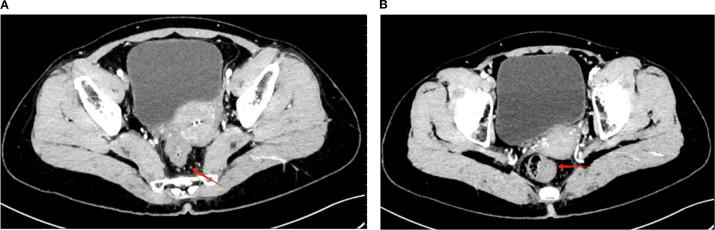

Microsatellite-stable (MSS) rectal adenocarcinoma remains a therapeutic challenge, particularly in patients with complicating factors such as chronic hepatitis B virus (HBV) infection. Advances in immunotherapy, including immune checkpoint inhibitors (ICIs), have introduced new opportunities to improve the treatment outcomes in this subset, yet their application in HBV-positive cancer patients is less well understood. Here we report the case of a 46-year-old female with MSS locally advanced rectal adenocarcinoma and active HBV infection, successfully treated with cmFOLFOXIRI combined with camrelizumab as neoadjuvant therapy. The patient presented with a circumferential rectal mass, elevated tumor markers, and virological evidence of high HBV viral load, necessitating prophylactic antiviral management with entecavir. Following five cycles of cmFOLFOXIRI and two cycles of camrelizumab, significant tumor regression was achieved, with further response observed after long-course radiotherapy combined with irinotecan and capecitabine. Laparoscopic low anterior resection revealed complete pathological remission (pCR), with no residual tumor cells or lymph node metastases identified. This case underscores the potential of integrating immunotherapy into multimodal neoadjuvant regimens for MSS rectal cancer while highlighting the critical importance of HBV management to minimize reactivation risks during treatment. These findings offer valuable insights into the safe and effective use of ICIs in HBV-positive cancer patients, warranting further investigation in larger clinical studies.

微卫星稳定(MSS)的直肠腺癌仍然是一个治疗挑战,尤其是对于伴有慢性乙型肝炎病毒(HBV)感染等复杂因素的患者。免疫疗法的进展,包括免疫检查点抑制剂(ICI),为改善这一亚组患者的治疗结果带来了新机遇,但其在HBV阳性癌症患者中的应用仍了解较少。在此,我们报告一例46岁女性患者,患有MSS局部晚期直肠腺癌且伴有活动性HBV感染,接受了cmFOLFOXIRI联合卡瑞利珠单抗作为新辅助治疗并获得成功。该患者表现为直肠环周肿物、肿瘤标志物升高以及HBV病毒载量高的病毒学证据,因此需要使用恩替卡韦进行预防性抗病毒治疗。经过五个周期的cmFOLFOXIRI和两个周期的卡瑞利珠单抗治疗后,肿瘤显著退缩,在接受长程放疗联合伊立替康和卡培他滨治疗后观察到进一步缓解。腹腔镜下低位前切除术显示完全病理缓解(pCR),未发现残留肿瘤细胞或淋巴结转移。该病例强调了将免疫疗法纳入MSS直肠癌多模式新辅助治疗方案的潜力,同时突出了HBV管理对于将治疗期间再激活风险降至最低的至关重要性。这些发现为在HBV阳性癌症患者中安全有效地使用ICI提供了有价值的见解,值得在更大规模的临床研究中进一步探究。